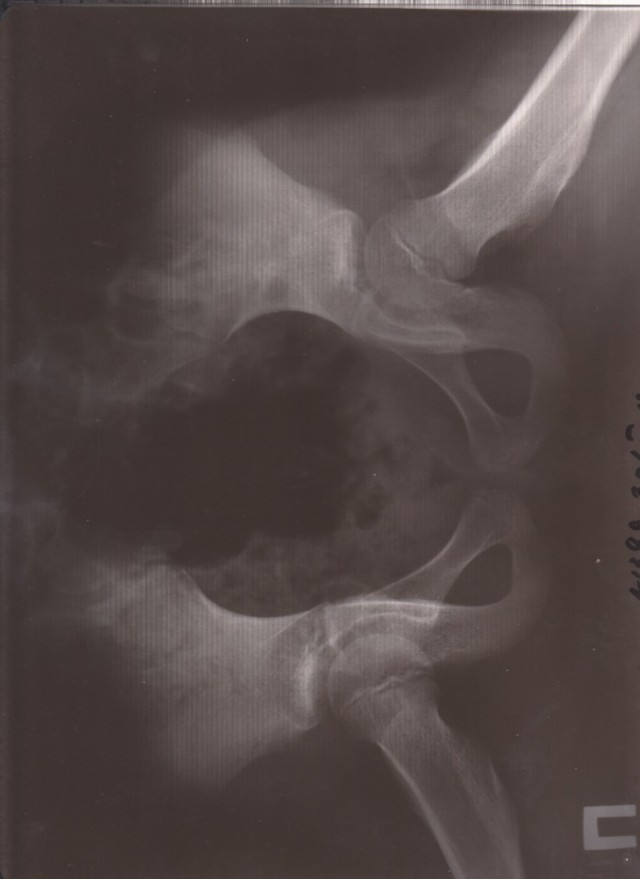

Пихнул, для интересу, снимки старые в обычный принтер. И ни че го. Черное поле и надпись фломастером по прозрачному краю. Так что не вариант.

С открытой крышкой такой же результат. А вот если открыть крышку и посветить фонарем что то проглядывает, но свет нужен яркий и равномерный.В принципе можно извернуться...

йа поэксперементировал и более менее результата добился подсвечивая вспышками двух телефонов.

Ну значицца вердикт- на бытовом сканере крышка открыта,свет как можно ярче, установки сканера- цветные, разрешение 300 уже хватает.

300 всё-же мало, думаю надо побольше, но файл получится тяжёлый. Ещё полосы получились вертикальные, но это ерунда, вся нужная информация видна. Яркость+ Контрасность+